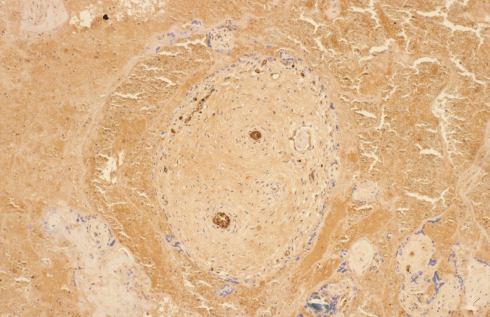

The term “Breus mole” is a combination of the eponym of the author of an early paper in German describing the lesion and the term “mole” for a hill or mass. The older terms like tuberose and fleshy mole are very descriptive, but no longer used. I prefer to use “Breus mole” rather than the common descriptive nosology of massive subchorionic (or subchorial) thrombohematoma, which is a confusing term. First, a Breus mole is within the chorion (the placenta is also called the chorion frondosum), but beneath the fetal surface of the chrorion (similar to a submarine, which is below the surface of the water, but not below the bottom of the ocean). A retroplacental hematoma is truly under the placenta. Some confusion exists about the term “subchorionic” in publications particularly of ultrasonographic observations(1-3). Secondly, the term thrombohematoma is in some ways a contradiction of terms. I was once denigrated in court by another placental pathologist for using the term. The problem is that a thrombus forms in a space with flowing blood, but a hematoma forms outside of the vascular system. Breus mole is a special case that combines features of both a thrombus from blood flowing in the intervillous space, and as a hematoma expanding the placenta. Microscopically, the blood shows sparse strands of fibrin confirming the presence of flowing blood in its formation (Fig 3)

Fig 3 This very low magnification photomicrograph shows the fetal surface of the placenta with surface chorionic vessels on the left of the photograph with a thrombohematoma below. Lines of fibrin lamination can be seen in the thrombohematoma (H&E).

Fig 25: This very low magnification photomicrograph shows the fetal surface of the placenta with surface chorionic vessels on the left of the photograph with a thrombohematoma below. Lines of fibrin lamination can be seen in the thrombohematoma (H&E).